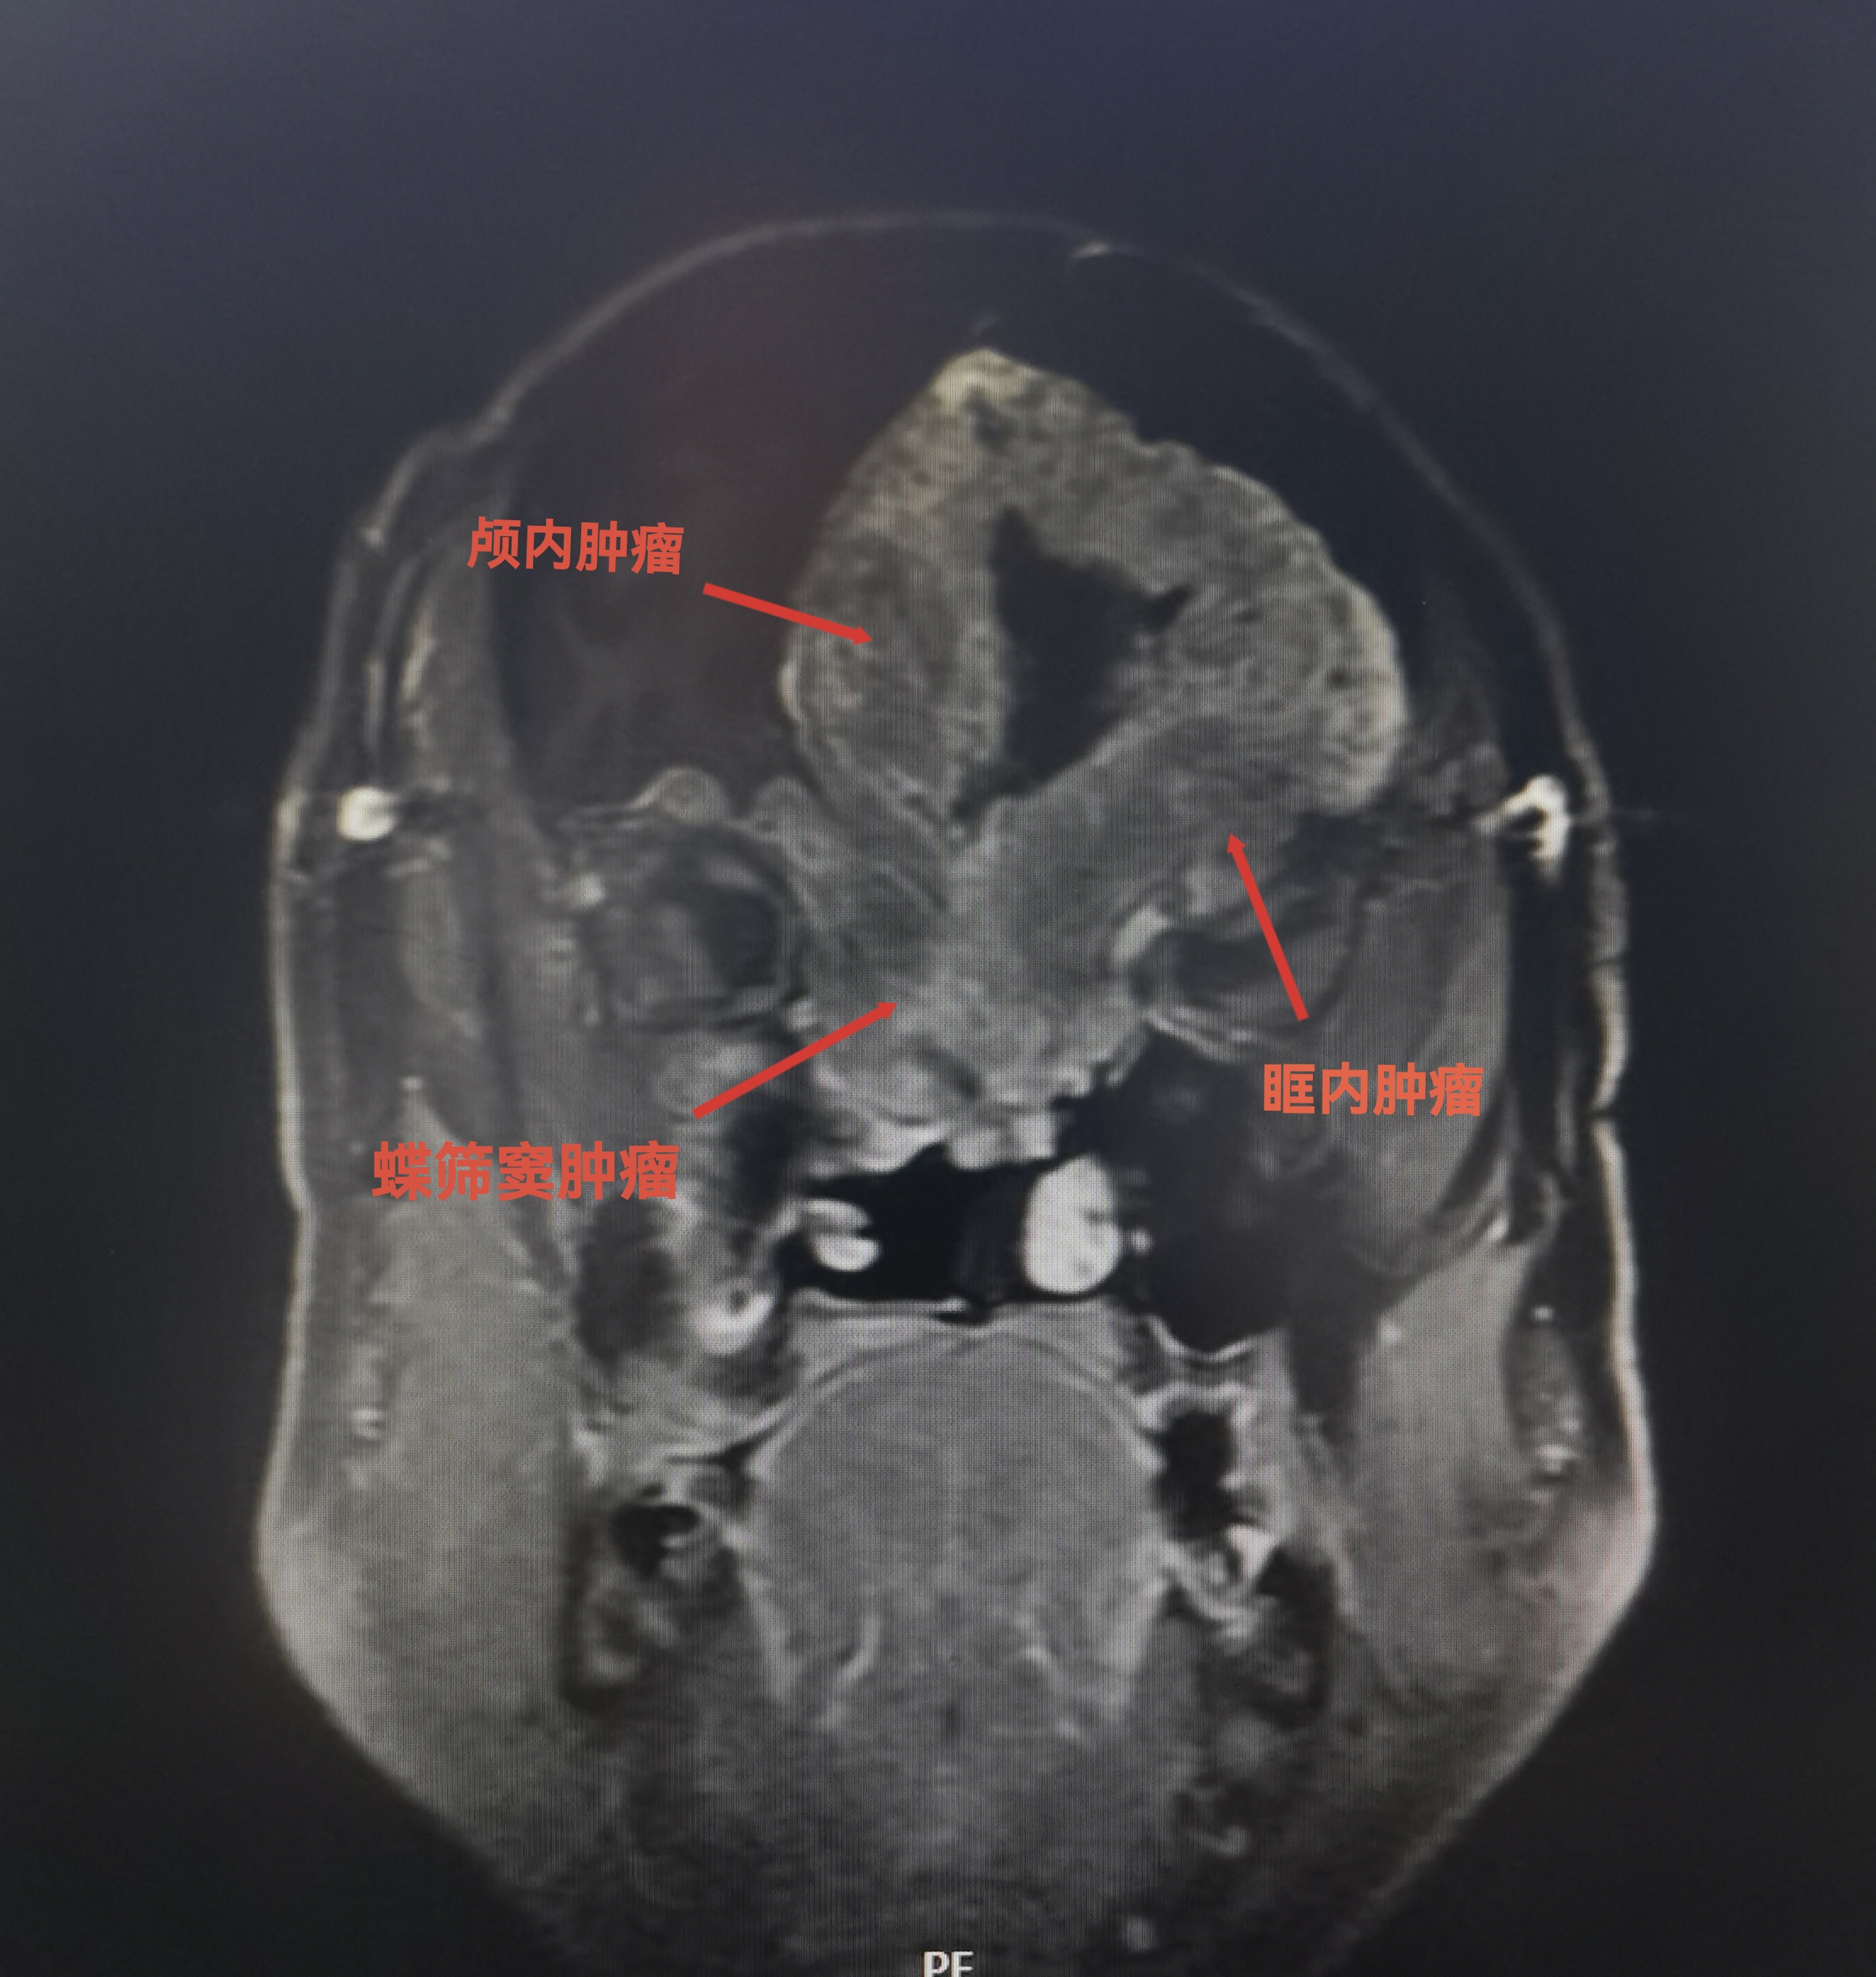

MRI可见肿瘤巨大,中鼻道以上,蝶窦筛窦及双侧额底均为肿瘤组织占据,向两侧到蝶骨嵴。肿瘤分叶状,可明显增强,核心区有坏死。后部可见粗大的静脉。双侧大脑前动脉位于肿瘤的后部。

肿瘤侵及颅鼻眶

肿瘤向后到鞍结节前床突,向外到两侧的蝶骨嵴。